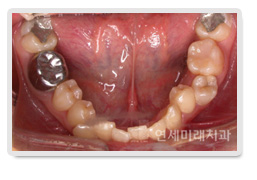

À½½Ä¹°ÀÌ Àß ¾ÃÈ÷Áö ¾Ê´Â °æ¿ìÀÇ ¿øÀÎÀº ¿©·¯ °¡Áö°¡ ÀÖ½À´Ï´Ù. (1) ´Ü¼øÈ÷ Ä¡¾Æ°¡ Çѵΰ³ ¾ø´Â °æ¿ì (2) Ä¡¾Æ°¡ ¾²·¯Áö°Å³ª ±â¿ï¾îÁ® ÀÖ´Â °æ¿ì (3) À´Ï¿Í ¾Æ·§´ÏÀÇ ±³ÇÕ °ü°è°¡ ÁÁÁö¾ÊÀº °æ¿ì (4) ±ÙÀ°À̳ª °üÀý¿¡ ¹®Á¦°¡ ÀÖ´Â °æ¿ì »çÁøÀÇ Áõ·Ê´Â ¾Æ·¡Å«¾î±Ý´ÏÀÇ À¯ÂøÀ¸·Î ÀÎÇØ¼ ÀÛÀº¾î±Ý´Ï¿Í Å«¾î±Ý´Ï°¡ Çϳª¾¿ ÀÕ¸ö¹ÛÀ¸·Î ¸ÍÃâÇÏÁö ¸øÇϰí, µÎ ¹øÂ° Å«¾î±Ý´Ï´Â ¾ÕÀ¸·Î ¾²·¯Á® Á¤»óÀûÀÎ ÀúÀÛȰµ¿ÀÌ ¾î·Á¿î °æ¿ìÀÔ´Ï´Ù

À¯ÂøµÈ Å«¾î±Ý´Ï¸¦ ¹ßÄ¡Çϰí ÀÛÀº¾î±Ý´ÏÀÇ ¸ÍÃâÀ» À¯µµÇÏ¿´°í, ±³Á¤ÀûÀ¸·Î´Â Àü¹æÀ¸·Î ¾²·¯Áø µÎ ¹øÂ° Å«¾î±Ý´ÏÀÇ °æ»çµµ °³¼±¹× Àü¹æÀ̵¿ ½ÃÅ´À¸·Î½á ÀúÀÛ±â´ÉÀ» ȸº¹½ÃÄÑ µé¸±¼ö ÀÖ¾ú½À´Ï´Ù. ÀúÈñ ¿¬¼¼¹Ì·¡Ä¡°ú¿¡¼´Â Ä¡¾Æ°¡ Çѵΰ³ °á¼ÕµÇ°Å³ª ¹ßÄ¡ÇØ¾ß ÇÏ´Â °æ¿ì, ÀÓÇöõÆ®³ª º¸Ã¶Ä¡·á¸¦ ÇÏÁö ¾Ê°í ±³Á¤ÀûÀ¸·Î Ä¡¾Æ¸¦ À̵¿½ÃÄѼ °ø°£À» Æó¼âÇÏ´Â Ä¡·áµµ ÇØ µå¸®°í ÀÖ½À´Ï´Ù.